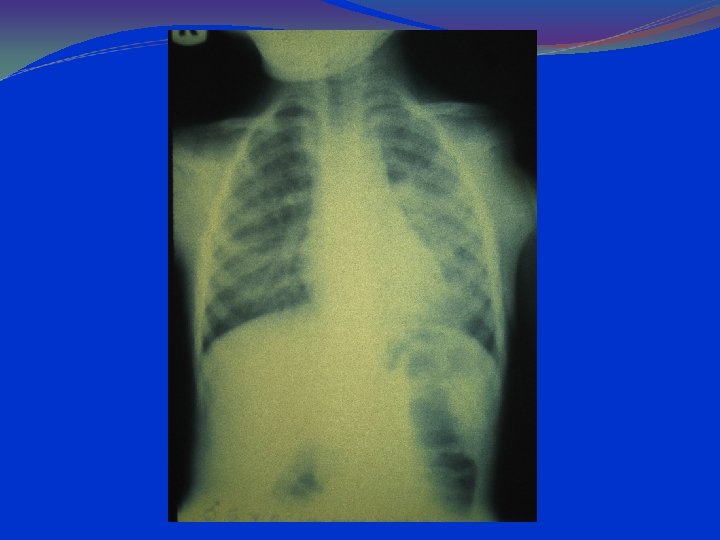

Bronchiolitis young infants, aged 2 -24 months. viral infection of the small airways (bronchioles). increased mucus secretion, cell death followed by a peribronchiolar lymphocytic infiltrate and submucosal edema debris and edema produce narrowing and obstruction of small airways. decreased ventilation in the lung causes ventilation/perfusion mismatching and hypoxia. in expiratory phase of respiration, further dynamic narrowing of the airways produces disproportionate airflow decrease and resultant air trapping.

Pathophysiology The virus spreads from the upper respiratory tract to the medium and small bronchi and bronchioles, causing epithelial necrosis and initiating an inflammatory response. The developing edema and exudate result in partial obstruction, which is most pronounced on expiration and leads to alveolar air trapping. Complete obstruction and absorption of the trapped air may lead to multiple areas of atelectasis

lung hyperinflation with a flattened diaphragm and bilateral atelectasis in the right apical and left basal regions

LABORATORY AND IMAGISTICS Complete blood count (CBC) with white blood cell (WBC) count within normal limits. 2/3 of the children have WBC counts of 10, 000 to 15, 000/μL. Most have 50 to 75% lymphocytes Serum chemistries may be affected in dehydration. Arterial blood gases (ABG) in severely ill patients, with mechanical ventilation. Chest radiographs should include anterior-posterior (AP) and lateral views. Hyperinflation and patchy infiltrates ; these findings are nonspecific and may be observed in asthma, viral or atypical pneumonia, and aspiration. Focal atelectasis Air trapping Flattened diaphragm Increased anteroposterior diameter